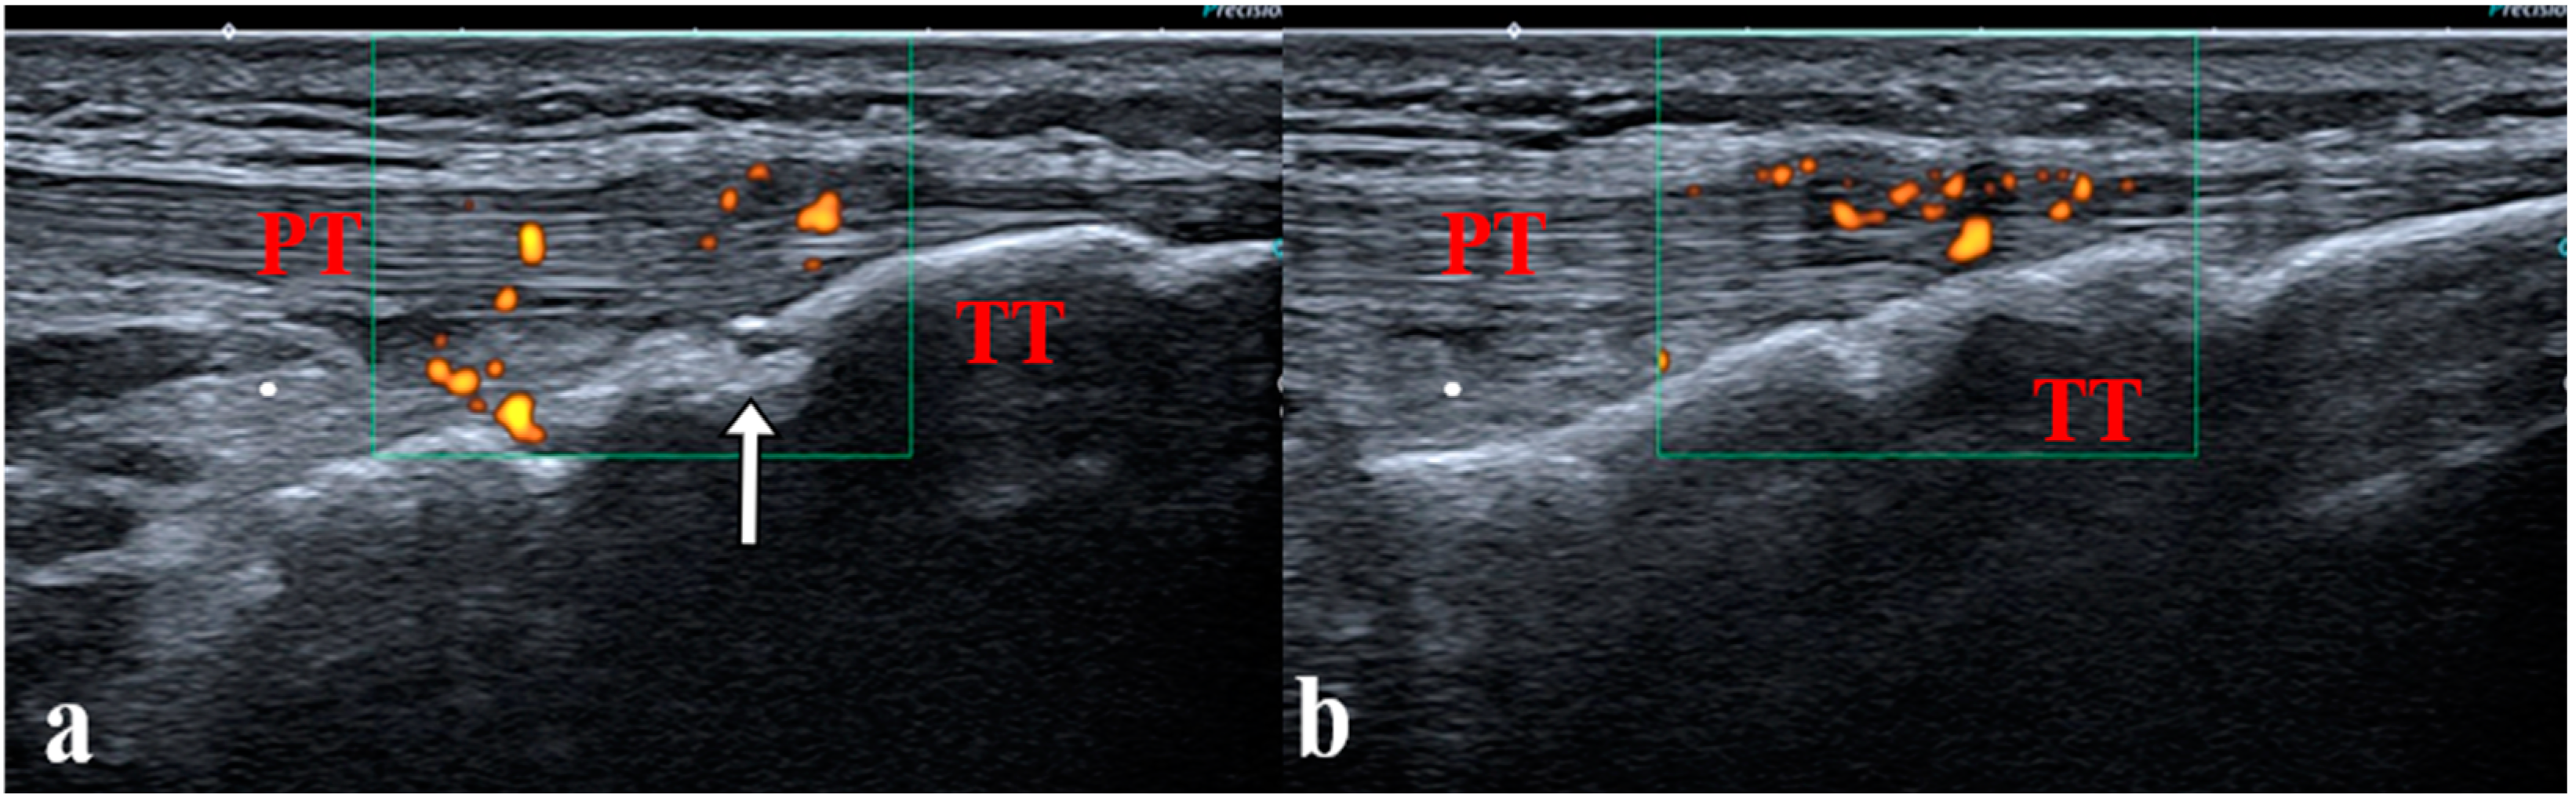

- Young, C.M.; Horst, D.M.; Murakami, J.W.; Shiels, W.E. Ultrasound-Guided Corticosteroid Injection of the Subtalar Joint for Treatment of Juvenile Idiopathic Arthritis. Pediatr. Radiol. 2015, 45, 1212–1217. [Google Scholar] [CrossRef] [PubMed]

- Laurell, L.; Court-Payen, M.; Nielsen, S.; Zak, M.; Fasth, A. Ultrasonography and Color Doppler in Juvenile Idiopathic Arthritis: Diagnosis and Follow-up of Ultrasound-Guided Steroid Injection in the Wrist Region. A Descriptive Interventional Study. Pediatr. Rheumatol. Online J. 2012, 10, 11. [Google Scholar] [CrossRef] [PubMed]